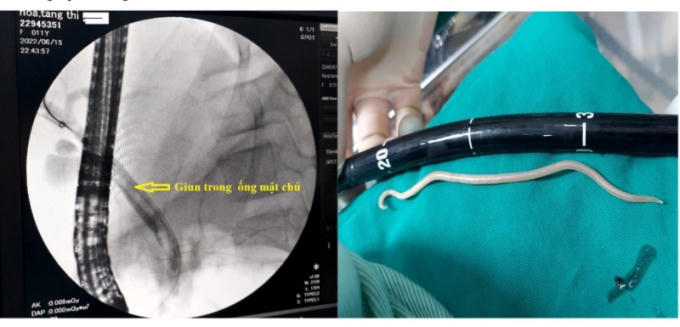

Ngày 18/6, theo thông tin từ Bệnh viện Bãi Cháy tỉnh Quảng Ninh cho biết, đơn vị vừa tiến hành nội soi mật tụy ngược dòng gắp thành công 1 con giun đũa dài gần 20cm trong ống mật chủ của bệnh nhi 11 tuổi.

Kíp nội soi Bệnh viện Bãi Cháy tiến hành thủ thuật gắp giun cho bệnh nhân nhi.

Bệnh nhi được đưa lên phòng can thiệp, bác sĩ đã tiến hành chụp đường mật qua màn tăng sáng C- Arm, xác định chính xác giun trong ống mật chủ và quyết định cắt cơ Oddi tối thiểu, dùng bóng kéo giun ra ngoài tá tràng, sau đó giun tiếp tục được lấy ra ngoài bằng rọ, thủ thuật kết thúc an toàn.

Hình ảnh giụ trong ống mật trên màn hình tăng sáng C-Arm và giụ sau khi được lấy ra ngoài.